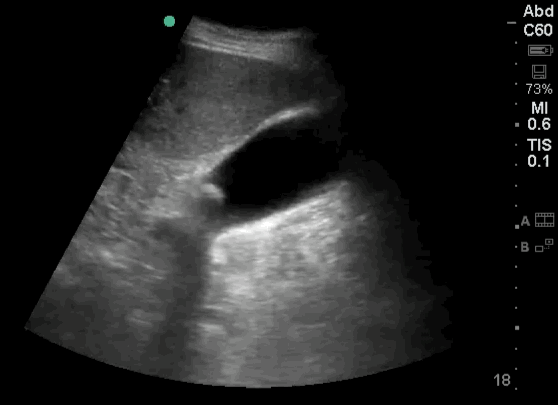

- Is free fluid present at the free edge of the liver ?